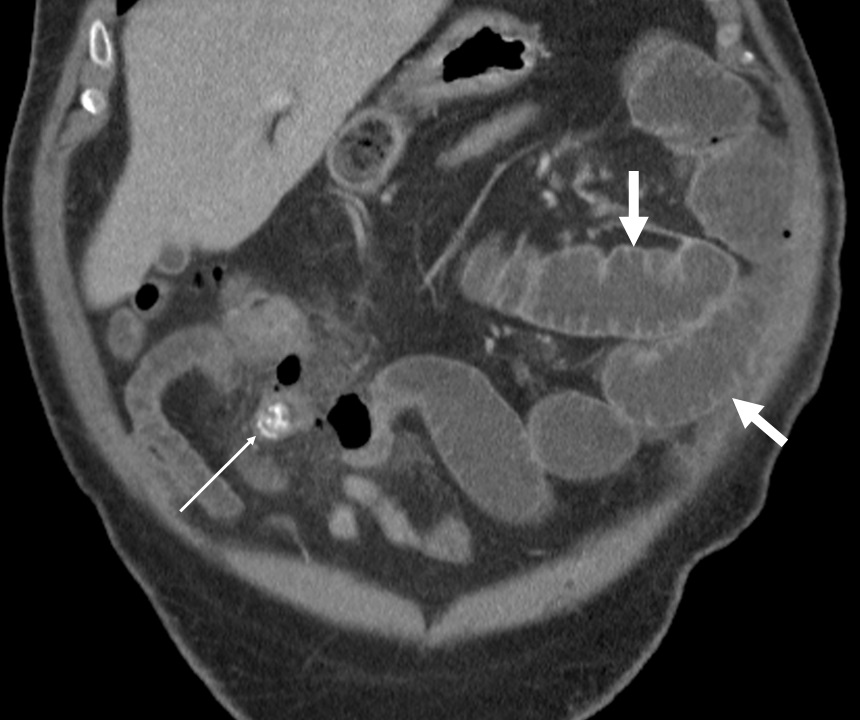

El divertículo de Meckel es la anomalía congénita más frecuente del tracto gastrointestinal, es un divertículo verdadero, ya que contiene todas las capas de la pared intestinal. Suele ser asintomático o se detecta de manera incidental en las pruebas de imágenes diagnósticas. Tiene un riesgo de complicación del 2-40%, siendo la más frecuentes la hemorragia, la obstrucción intestinal y la diverticulitis.

Se describe el caso de un paciente masculino de 52 años de edad, que consultó al servicio de urgencias del Hospital Universitario de Salamanca (España) por un cuadro de dolor abdominal, clínica infecciosa y  de obstrucción intestinal.

Mediante pruebas de imagen se diagnosticó una obstrucción intestinal secundaria a diverticulitis de Meckel por un enterolito, se realizó intervención quirúrgica y se confirmaron los hallazgos radiológicos descritos.